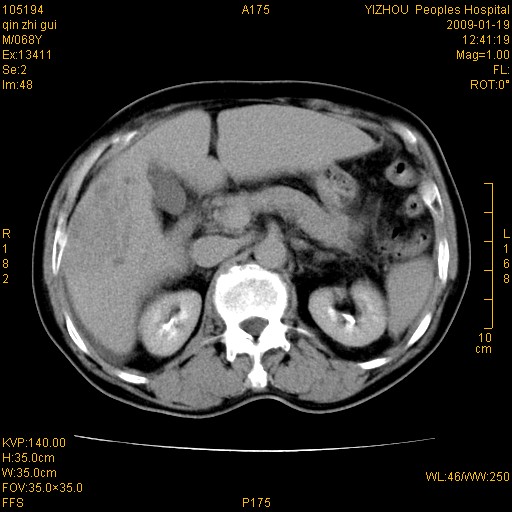

以下是引用随光逐影在2009-1-21 16:11:00的发言:[br]1)考虑肝右叶肝癌并肝静脉及门静脉瘤栓形成。2)肝硬化,少量腹水。3)胆囊炎。4)右侧少量胸腔积液。

病灶外缘凹凸不平,平扫低密度,增强动脉期有强化,门脉早显,静脉期及延期呈延迟强化,结合病史考虑右肝前叶巨块型肝癌可能性大,强化表现不除外胆管细胞癌